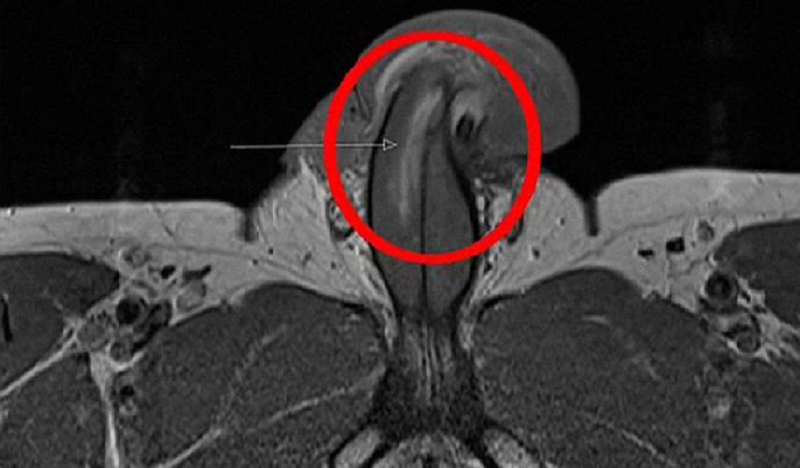

Mas, neste caso, ele dividiu a túnica albugínea – a camada protetora em torno do tecido erétil que bombeia o sangue para essa área.

O médico disse que nenhum som de “estalo” foi ouvido quando a quebra ocorreu, o que acontece quando as fraturas são horizontais.

Mas o pênis do paciente gradualmente inchou após o ferimento.